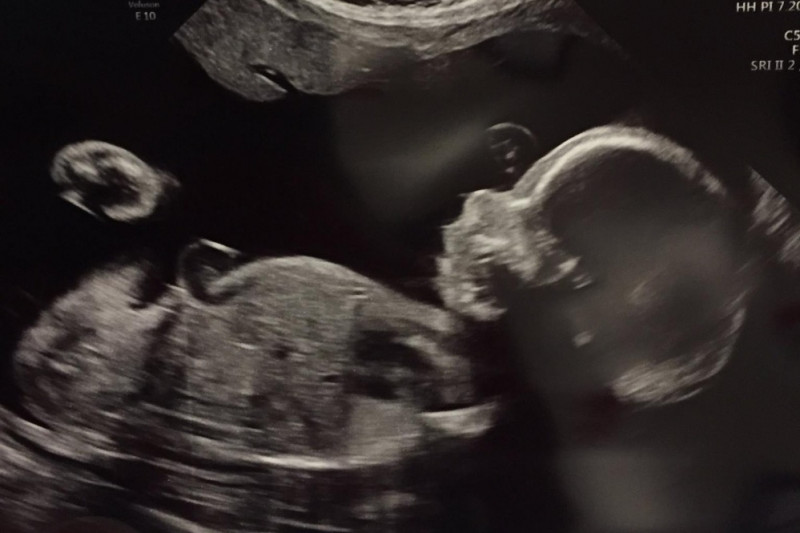

Noah has a condition called CPAM (Congenital Pulmonary Airways Malformation). Basically he has a mass in his chest that has many large cysts which could cause complications with his heart, among other things. While we were hoping the mass wouldn't grow during the pregnancy, it has, meaning Amanda has to make occasional trips to a hospital several states away.